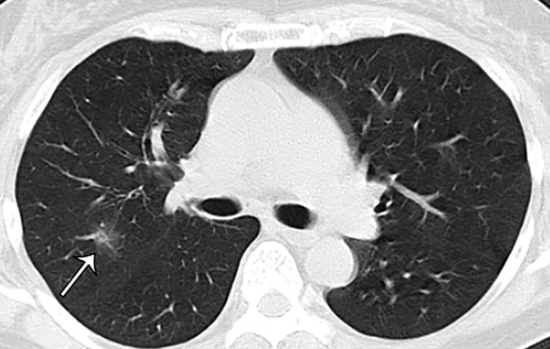

У переболевших коронавирусом без симптомов обнаружены поражения легких - об этом говорится в исследовании японских ученых, которые проанализировали состояние 104 заразившихся COVID-19 пассажиров лайнера Diamond Princess.

Японцы изучали результаты компьютерной томографии.

И у больше, чем половины - 41 человека из этих "бессимптомных" по результатам КТ обнаружились изменения в легких (так называемый "эффект матового стекла").